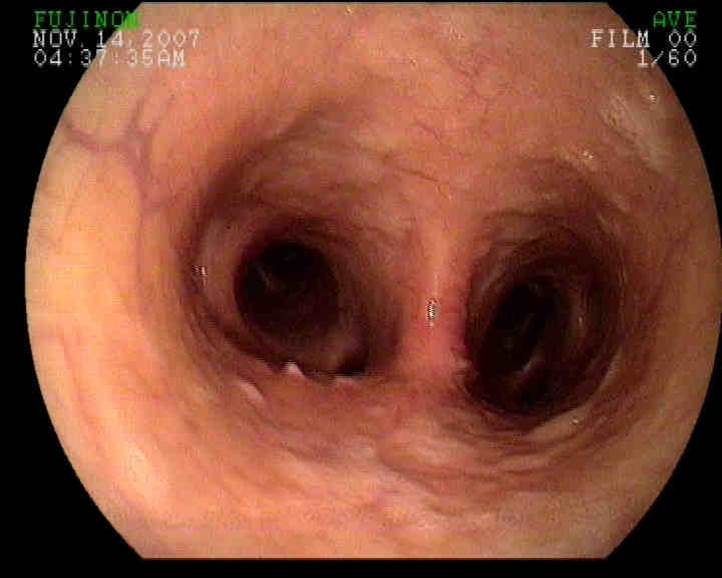

When I examined the horse, the gelding was in distress! His heart rate was 80 bpm, respiratory rate was 60-70 bpm (shallow) and his body temperature was 102 degrees. Auscultation of the thorax noted lung sounds (sound of air moving in and out of lungs) on both sides of the horse only ABOVE the level of the shoulder but lung sounds were absent or muffled below the level of the shoulder. Suspecting pleuropneumonia, I performed a trans-thoracic ultrasound exam. A significant amount of fluid was noted in the pleural space along with large fibrin tags and multiple abscesses! ( Figure 1-3).

In the video clips below, the fibrin tags can be seen "floating" in the excessive fluid within the pleural space. In addition, the fluid appears as "cellular" suggesting a heavy component of fibrin and purulent debris (pus).

In Figure 2-3, large abscesses are noted adjacent to the body wall. Ultimately, these abscess would need to be exteriorized through a rib resection in order for the horse to completely heal. Unfortunately, the ultrasound findings combined with the severe physical distress were very poor prognostic indicators and the owner elected humane euthanasia! There was near zero chance that this horse could have been saved regardless of the medical and surgical intervention provided!